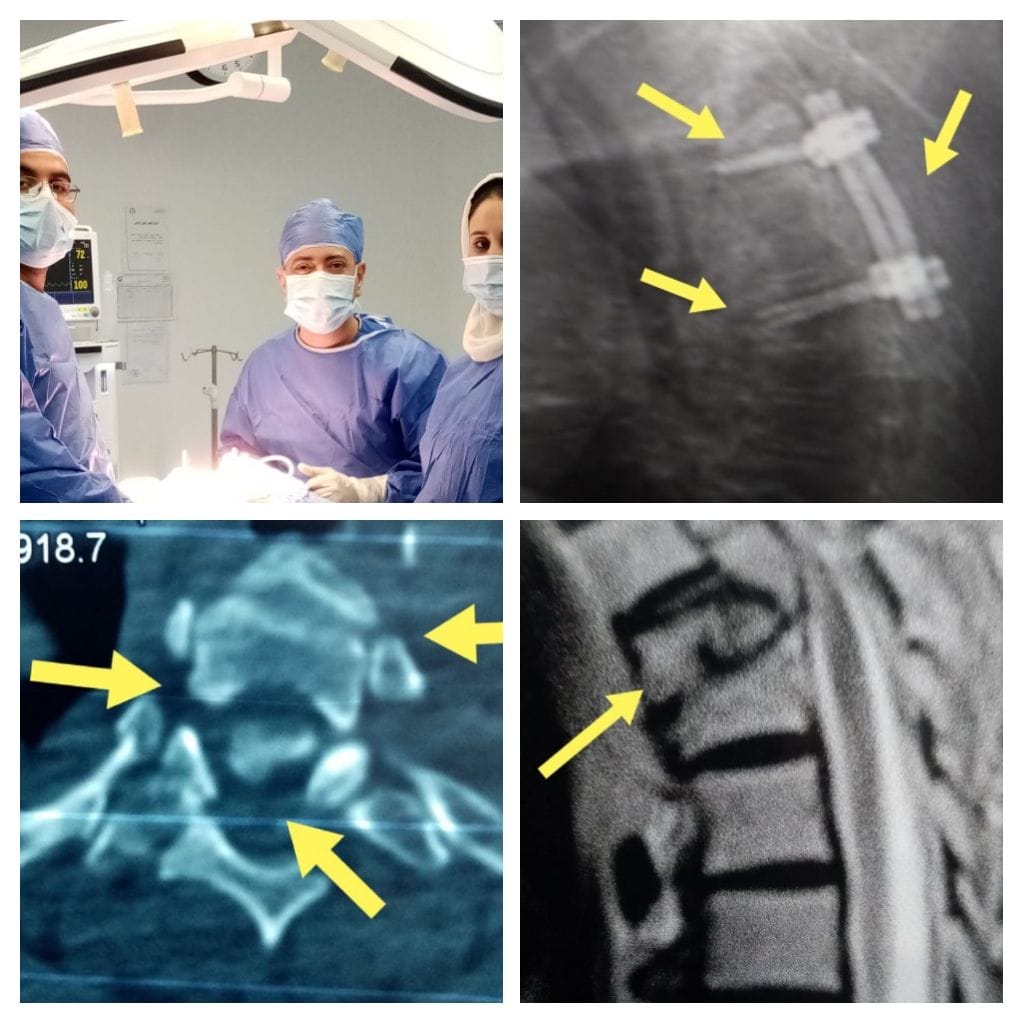

فريق جراحي بمستشفى كفر شكر التخصصي ينقذ مسنة مصابة بكسور بالفقرات الصدرية

جانب من الجراحة

قام فريق جراحة المخ والأعصاب بمستشفى كفر شكر التخصصي بمحافظة القليوبية ، بالتجهيز وإدخال مسنة 60 عاما مصابة بكسور بالفقرات الصدرية لغرفة العمليات فى الواحدة صباحا لتستمر العملية حتي الفجر، ويتم إنقاذ النخاع الشوكي والأعصاب الطرفية من شظايا الكسر ، والتي أدت إلى تهتك وكدمة شديدة بالحبل الشوكى، وتثبيت الفقرة الضاغطة على الحبل الشوكي بمنطقة الفقرات الصدرية.

وقام الفريق الطبى بإجراء الجراحة وذلك باستخدام جهاز لتثبيت الكسر تحت الأشعة المرئية، بتوجيه كبير فنيين الأشعة علاء والتي كان من الممكن أن تؤدي إلى حدوث شلل بالطرفين السلفيين للمصاب، وتعد تلك العملية هي الأولى بمستشفى كفر شكر التخصصي، لتثبيت كسر متفتت ضاغط على الفقرة الثالثة الصدرية.